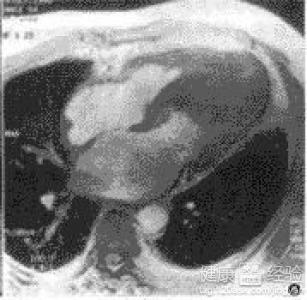

摘要:關(guān)于擴張性心肌病的最新治療,小巷深處的隱藏寶藏正逐漸為人們所發(fā)現(xiàn)。通過先進的醫(yī)療技術(shù)和方法,擴張性心肌病的治療取得了新的進展。這些治療方法旨在改善心臟功能,提高患者生活質(zhì)量。小巷深處的醫(yī)療機構(gòu)或?qū)<铱赡茈[藏著寶貴的治療經(jīng)驗和方法,為尋求最佳治療方案的病患帶來希望。更多詳細信息需要進一步探索和研究。